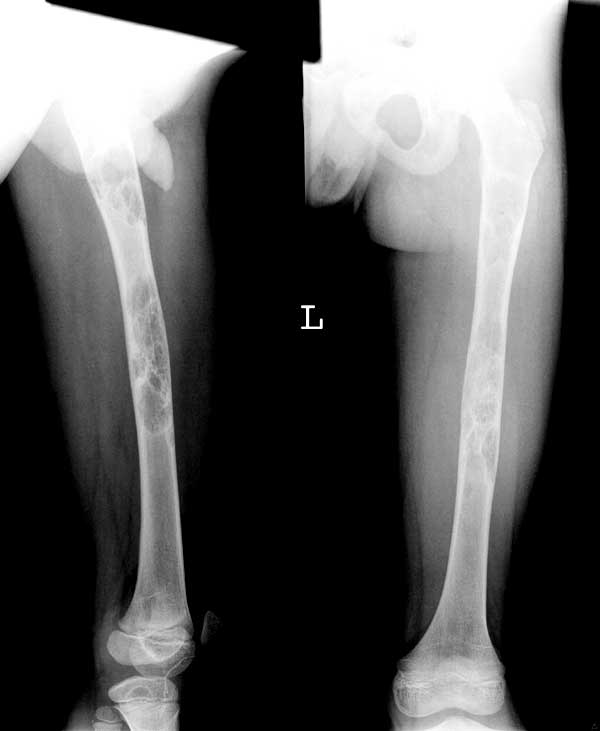

右股骨干病理骨折.

股骨干较大范围膨胀性骨破坏[两处] ,其内见丝瓜瓤改变,皮质变薄,

骨纤维异常增殖征

股骨干较大范围膨胀性骨破坏与骨长轴走行伴病理性骨折,皮质变薄,,其内见丝瓜瓤样与磨玻璃样改变,皮质变薄,又是小儿考虑骨纤维结构不良,骨囊肿待排。

股骨干膨胀性破坏内见丝瓜瓤改变,皮质变薄,还是考虑骨纤

病变范围较大,呈不均匀性膨胀性囊性低密度,且不均匀,内有间隔。考虑:1,骨纤维异常增殖症 2,甲状旁腺机能亢进不排除。[emb18]

股骨干轻度膨胀,内有多个囊状透亮区及磨玻璃样影,右胫骨上端亦有小囊状影。

诊断:骨纤维异常增殖症。

病灶多发,范围较广,呈丝瓜襄样,还是考虑骨纤